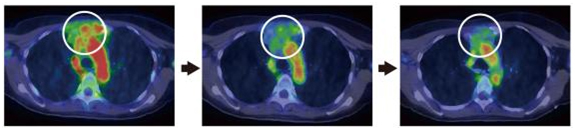

臨床試験では、既にHER2陽性であることが確認され、トラスツズマブで治療中の乳がん患者の協力を得ました。文書による臨床試験への参加同意が得られた患者14症例に対して、通常治療用量の100分の1以下※9に相当する64Cu-DOTA-Trastuzumabを静脈注射し、6、24、48時間後にPET検査を行いました。その結果、最小直径2.0cmまでの腫瘍を描出できることが分かり、ほとんどの症例でHER2陽性乳がんの原発巣に一致したシグナルを観察しました(図2)。転移巣の診断では、特に脳転移の描出に優れることが分かりました(図3左)。針生検でHER2陽性乳がんの肺転移が確定した症例では、転移巣の位置にシグナルを認め、針生検と画像診断の結果が一致することを確認しました(図3右)。また胸骨/縦隔リンパ節転移症例では、治療に伴いがん組織が縮小する様子を追跡できました(図4)。さらに、腎細胞がんとHER2陽性乳がんの両方のがんを有する症例(重複がん)では、HER2陽性脳転移巣が描出される一方、腎細胞がんではシグナルを認めず、今回のPET検査がHER2陽性腫瘍を特異的に検出することが分かりました。

図4 トラスツズマブPETプローブで経過観察したトラスツズマブ治療の効果

胸骨および縦隔(左右の肺と胸椎、胸骨に囲まれた部分)に転移したHER2陽性乳がん患者に対するトラスツズマブ治療の効果を、64Cu-DOTA-Trastuzumabのシグナルで追跡した。治療が進むにつれて、HER2陽性腫瘍の縮小を確認した(白丸で囲んだ領域)。その下部は心臓内腔のシグナルを示す。左:治療前、中:治療第8サイクル(8週間)後、右:治療第16サイクル(16週間)後。